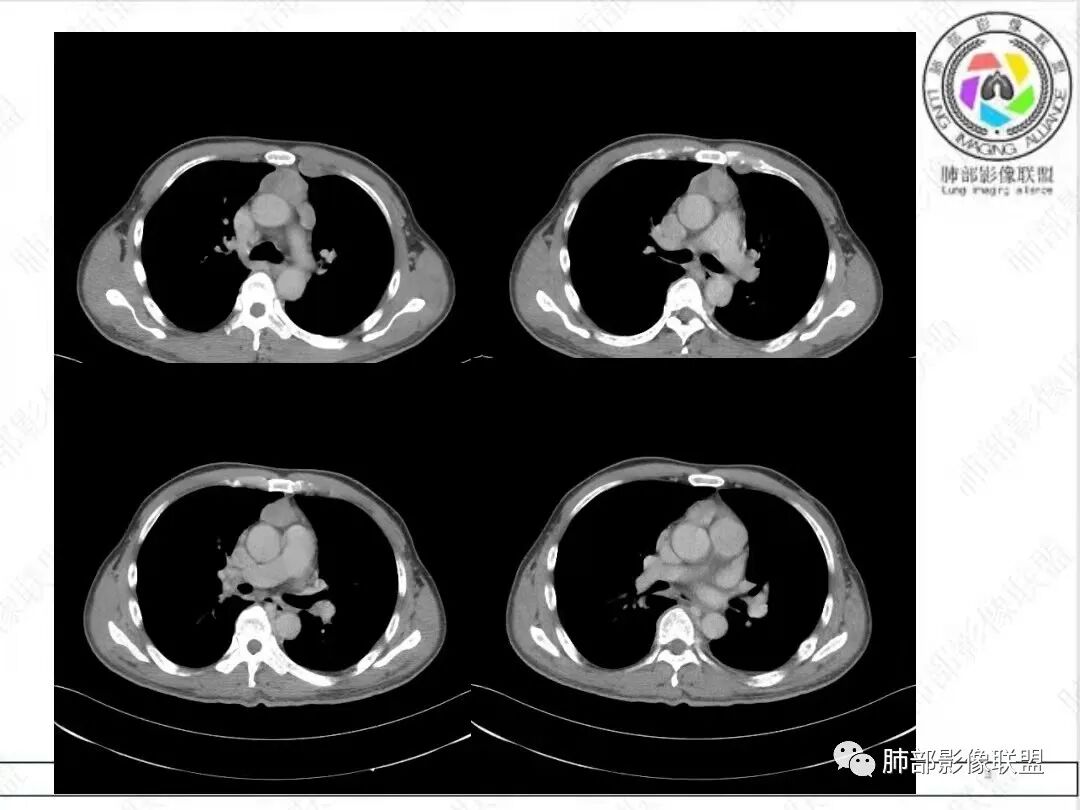

2、影像特点:胸部CT:平扫,前纵隔肿物,基本居中,与周围结构局部分界不清。增强后显示轻中度强化。肿块沿血管间隙侵袭性生长,左无名静脉受压明显变形受侵。纵隔、右肺门多处大小不等淋巴结,左侧内乳淋巴结稍增大。右侧瘤肺交界面光滑,左侧凹陷,肺组织未见明显受侵。右肺中下叶可疑小结节。胸椎及肋骨骨质增生性破坏。肋骨骨折。

病理结果:胸腺不典型类癌。

3、病例小结:  病人以胸痛就诊,无明显内分泌症状;前纵隔该部位肿瘤,胸腺瘤常见,乳酸脱氢酶偏高,55岁的年龄也较符合胸腺瘤,但胸腺瘤较少侵犯甚至包绕大血管生长、少有淋巴结肿大。

很多老师提到前纵隔占位+血管肿块内漂浮+内乳淋巴结增大+轻中度强化=淋巴瘤,淋巴瘤确有上述特点,但本例血管漂浮不明确,病灶强化不均匀,胸椎及肋骨可疑增生性转移,应想到胸腺癌或不典型类癌的可能性。

胸腺类癌好发于40~60岁男性,男女比例约为3:1。胸腺类癌侵袭性较胸腺癌低,属于低至中等程度恶性肿瘤。但是约80%侵犯邻近组织结构,20%~40%发生胸内淋巴结或远处转移,转移部位主要包括肺脏、骨、肝脏、脑等,一般表现为椎体成骨性转移。胸腺类癌影像特征:呈现纵隔偏侧性的生长,形态不规则,肿块体积通常较大,内见片状坏死区,增强扫描轻中度不均匀渐进性强化。肿瘤内部可见细丝状明显强化小血管影,推测此征象可能在胸腺类癌的诊断中有提示作用。肿瘤边界常不清晰,沿血管间隙侵袭性生长,易侵犯邻近纵隔大血管、心包、气管、食管等结构。钙化少见。